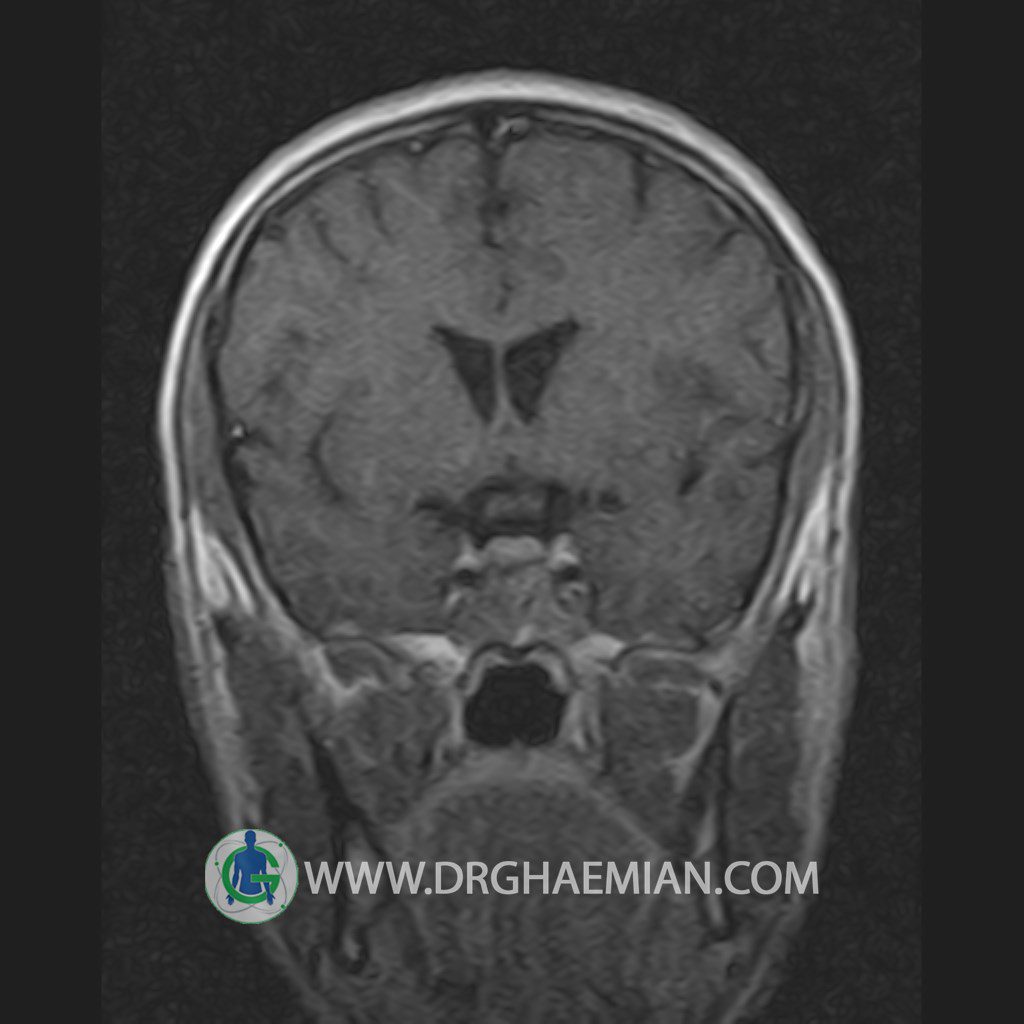

پزشکان اغلب از تصویربرداری ام آر آی برای تشخیص و درمان عارضه های پزشکی که فقط با استفاده از اشعه ایکس یا میدان مغناطیسی و امواج رادیویی قابل مشاهده است، استفاده می کنند. دستگاه ام آر آی تصاویر دقیق از ساختار های داخلی بدن ایجاد می کند. در این کیس یک میکروآدنوم در هیپوفیز بیمار مشاهده می شود.

HYPOPHYSIS MRI

(with and without contrast)

Technique: Axial , coronal T1 , Axial , coronal , sagittal T2 , Axial, coronal T1 post Gd & 64 dynamic thin coronal slices.

The infundibulum is centered and of normal size .

The optic chiasm and suprasellar spaces appear normal .

The cavernous sinus and imaged portions of the internal carotid artery and carotid siphon are unremarkable .

Evaluable portions of the neurocranium show no abnormalities .

The sphenoid sinus is clear and pneumatized .

Imaging of the hypothalamus after contrast medium administration was normal.

– Small hypoenhancing mass lesion ( 3 x 4 mm ) in posterior of pituitary stalk suggestive for micro adenoma

– Mucosal thickening in ethmoid & maxillary sinuses

is seen